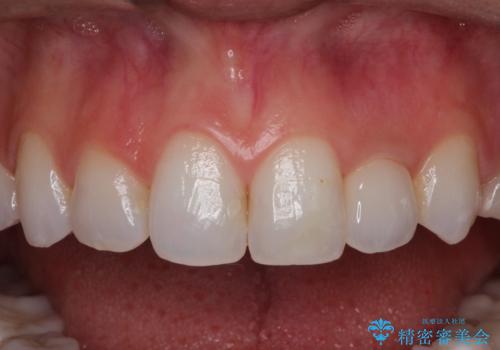

前歯の被せ物をやり替えたい

- 以前に被せ物の治療した箇所に汚れが溜まりやすいことを主訴に来院されました。

矯正治療を行なったのち、オールセラミッククラウンにて修復しております。

矯正治療はインビザラインで行なっております。